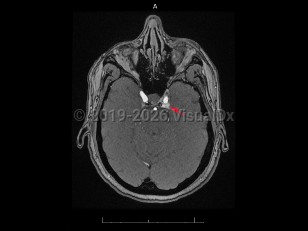

Carotid-cavernous fistula

Acquired vascular abnormality involving communication between the cavernous sinus and the carotid artery or branches. It may arise spontaneously or through injury by blunt head trauma, surgery, or vascular and connective tissue disorders, or following cavernous carotid aneurysm rupture. Onset may be delayed. Carotid-cavernous fistula (CCF) are classified as high-flow (direct) or low-flow (indirect), depending on the pressure and direction of the communicating arterial blood flow. Common symptoms include bruit, proptosis, diplopia, blurred vision, visual loss, conjunctival injection, eye pain, headache, and chemosis. CCF affects men and women about equally. Rarely, they appear bilaterally.

Treatment depends on the classification of the CCF, with endovascular obliteration being the first approach to closure, although multiple procedures may be necessary.